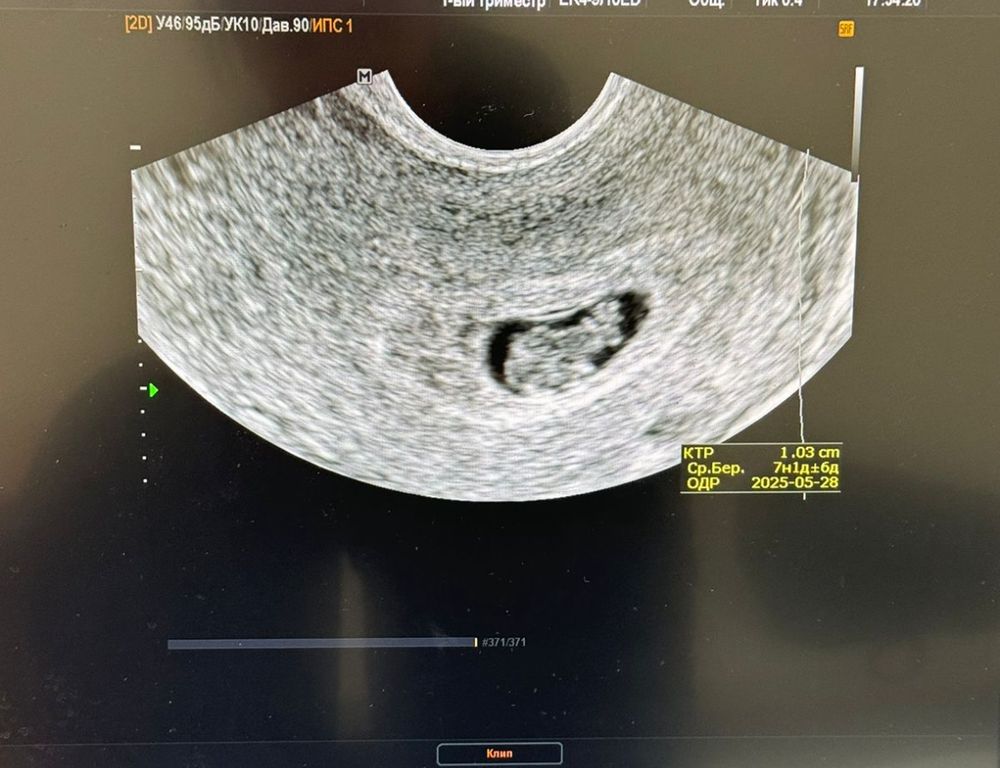

далее пошла на узи на сроке через 5 дней после первого , малыш заметно подрос, но не нашли сб, за день до узи начались легкие коричневые выделения, болей и тд нет. (УЗИ и фото прикрепляю 3.4)

При таком ктр сердцебиение не появляется, оно у 90% появляется при ктр до 4, у 10% 4-6. Можно переделать УЗИ для самоуспокоения, но надеяться можно только, что не увидели на УЗИ.